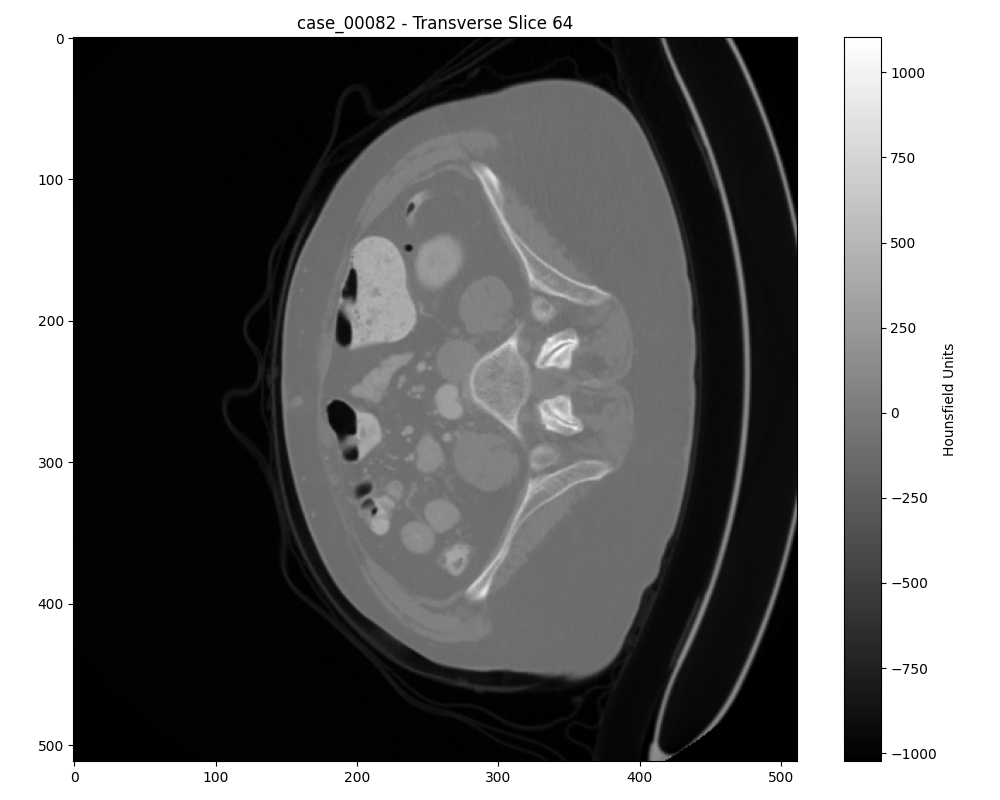

Axial slice of a malignant tumor

Axial slice of a benign tumor

Another axial slice of a benign tumor

Case 00104: Advanced malignant tumor with 3D volume visualization (top) and optimal 2D slice selection (bottom)

Additional Case Study: Malignant Tumor

Case 00082: Early-stage benign tumor with 3D volume visualization (top) and optimal 2D slice selection (bottom)

Additional Case Study: Benign Tumor